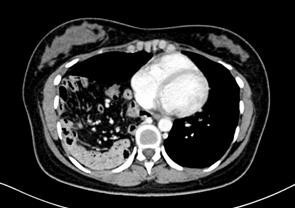

患者,女,26岁,2月前患者体检时发现“右侧胸腔斑片状影”(患者自述),复查CT发现为“右侧膈疝”,患者无特殊不适,无恶心、呕吐、大小便异常等。

查胸、腹部增强CT示“右侧膈疝;右肺明显受压伴少许炎症。左肺下叶基底段小结节,部分肠系膜、肠道及网膜疝入胸腔。肝脏形态失常,下腔静脉肝段变窄。左肾小囊肿”。

诊断:右侧膈疝。行膈疝修补术,手术顺利。